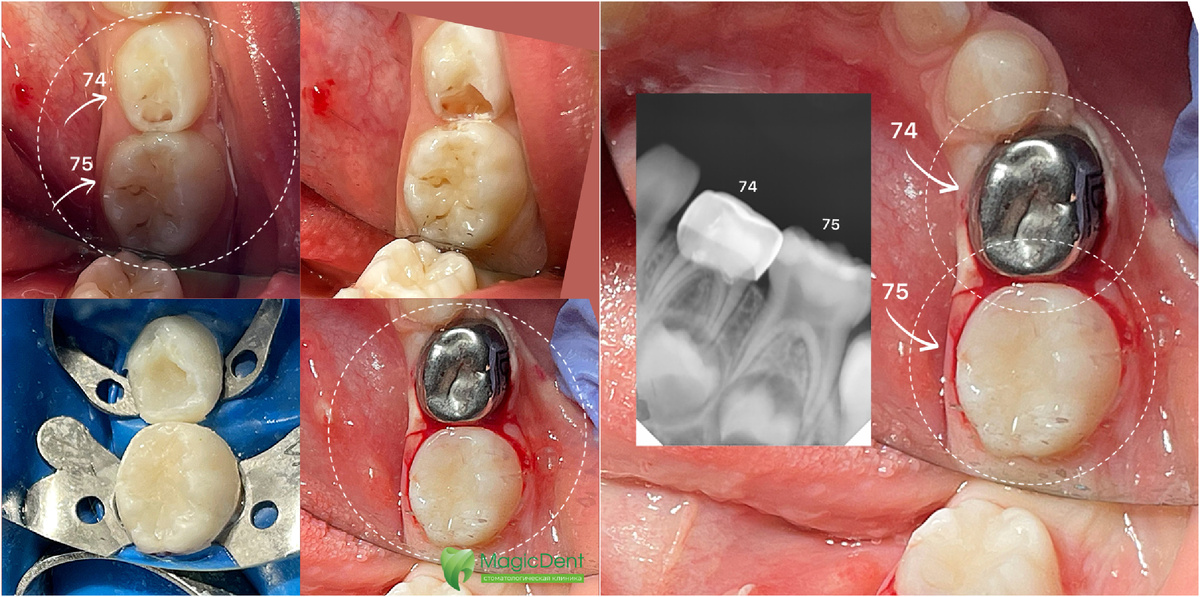

Кейс детского стоматологического лечения молочных зубов ( 74 и 75) в условиях седации закиси азота у ребенка 4-х лет. 75 зуб — лечение кариеса, реставрация материалом Harmonise A1, шлифовка, полировка. 74 зуб — лечение обратимого пульпита, покрытие зуба стандартной металлической коронкой 3М с фиксацией на цемент Fuji 9. Указанный объем лечения уложили в 1 час времени. Работа врача, детского стоматолога, стоматолога-терапевта, микроскописта, эндодонтиста, хирурга, Натальи Федоровны Горбуновой. 📍MAGIC DENT 354000 Краснодарский край, г. Сочи 8-804-700-15-15 (звонок бесплатный) -ул. Юных Ленинцев, д. 10, 2 этаж 📞тел. +7-918-165-15-15 magicdent.sochi@mail.ru -ул. Пластунская, д. 123А, корп.2, ЖК «123» 📞тел. +7-988-165-15-15 magicdent123@mail.ru https://mdsochi.ru #детскийстоматологсочи #детскаястоматологиясочи

Кейс детского стоматологического лечения молочных зубов ( 74 и 75) в условиях седации закиси азота у ребенка 4-х лет.

75 зуб — лечение кариеса, реставрация материалом Harmonise A1, шлифовка, полировка.

74 зуб — лечение обратимого пульпита, покрытие зуба стандартной металлической коронкой 3М с фиксацией на цемент Fuji 9.

Так выглядят уже пролеченные молочные зубы 74 и 75

Указанный объем лечения уложили в 1 час времени.